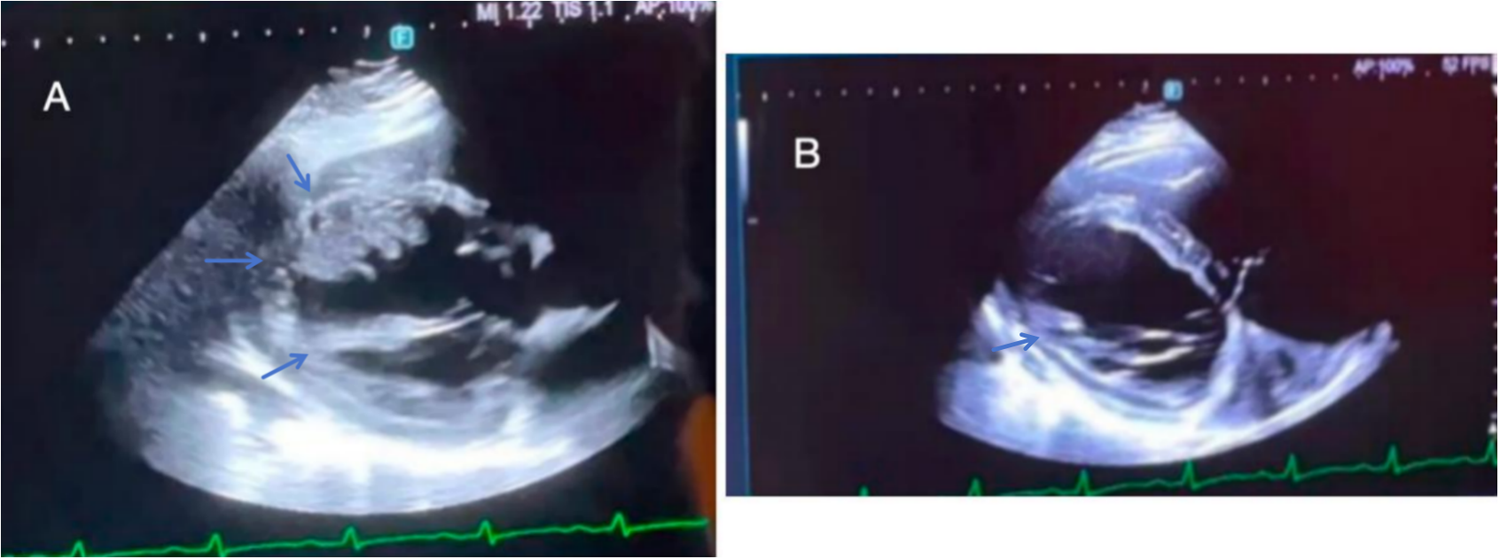

On the fourth day of hospitalization, sputum culture showed no bacterial/fungal growth, with improved inflammatory/myocardial enzyme/coagulation markers. pANCA/cANCA tests were negative. Ultrasonic cardiogram (UCG) (Figure 2A) revealed biatrial/right ventricular enlargement, left ventricular wall motion abnormalities, reduced LVEF (42%), mild left ventricular wall thickening (4 mm), intraventricular thrombus, and pericardial effusion. After 1 week of respiratory department treatment (anti-infection, LMWH anticoagulation, acid suppression, diuretics), chest CT (Supplementary Figure S1) demonstrated bilateral pulmonary infarctions with consolidations/infiltrates and small pleural effusions. Echocardiography showed further LVEF decline to 36% and rising BNP levels. The patient developed worsening dyspnea, orthopnea, and generalized edema, with unclear ventricular thrombus etiology, prompting transfer to cardiology for further evaluation.

Figure 2

(A) On the fourth day of hospitalization, UCG revealed biatrial/right ventricular enlargement, left ventricular wall motion abnormalities, reduced LVEF (42%), mild left ventricular wall thickening (4 mm), intraventricular thrombus, and pericardial effusion. (B) On the thirteenth day of hospitalization, UCG revealed an interventricular septum measuring 15 mm, an LVEF of 34%, reduced left ventricular thrombus and normal right heart function.

On hospital day 7, genetic testing revealed MTHFR C677T (CT genotype) and PAI-1 4G/5G polymorphism, indicating mild increased venous thrombosis risk from metabolic/fibrinolytic defects. By day 10, cardiac MRI showed interventricular septal thickening (13 mm), left atrial enlargement, and severe LVEF decline (26.5%). The sputum and pleural fluid was noted to be hemorrhagic (Supplementary Figure S2). Pleural fluid next-generation sequencing identified EBV/CMV, confirming viral myocarditis. Treatment added IV methylprednisolone (100 mg bid), transitioning to oral 1 mg/kg/day with gradual taper. By day 13, the patient reported resolved chest pain, improved edema, and cardiac ultrasound showed septal thickening (15 mm), LVEF 34%, persistent LV thrombus, and normal right heart function (Figure 2B). Despite ongoing anticoagulation, day 14 chest CT revealed progression of pulmonary infarcts, and the patient developed acute right limb weakness (lower limb Muscle strength grade 1) with scattered cerebral infarcts on neuroimaging (Supplementary Figure S3), without major vessel occlusion.